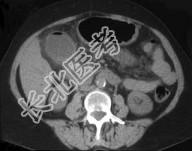

- 单项选择题患者50岁,右上腹痛, 结合图像,最可能的诊断是 ( )

A、气肿性胆囊炎

B、急性胆囊炎

C、慢性胆囊炎

D、胆囊癌

E、以上都不是